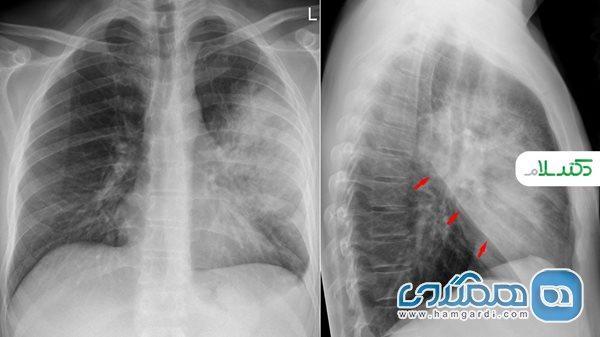

به گزارش مجله سرگرمی، مجله پزشکی دکتر سلام/پنومونیت یا پنومونیت به التهاب بافت ریه اشاره دارد. از نظر علمی پنومونی نوعی پنومونیت است زیرا عفونت باعث التهاب بافت شش ها می گردد. با این حال، پنومونیت به طور معمول توسط پزشکان برای اشاره به علل غیر عفونی التهاب ریه استفاده می گردد.

پنومونیت هنگامی رخ می دهد که ماده تحریک نماینده باعث التهاب کیسه های ریز هوا (آلوئول) در ریه های گردد که این التهاب عبور اکسیژن از آلوئول ها به جریان خون را سخت می نماید. بسیاری از عوامل تحریک نماینده از کپک های موجود در هوا گرفته تا داروهای شیمی درمانی با التهاب ریه در ارتباط هستند، اما برای بیشتر افراد ماده خاص ایجاد نماینده التهاب هرگز معین نمی گردد.

در صورت بی توجهی یا عدم درمان پنومونیت آسیب غیرقابل جبرانی در ریه ایجاد می گردد. در ریه های طبیعی کیسه های هوا با هر بار تنفس کشیده و شل می شوند. التهاب مزمن بافت نازک پوشاننده هر کیسه هوا باعث ایجاد زخم می گردد و انعطاف پذیری کیسه ها کمتر می گردد. آنها مانند یک اسفنج خشک سفت می شوند که فیبروز ریوی نامیده می گردد. در موارد شدید فیبروز ریوی باعث نارسایی قلب سمت راست، نارسایی تنفسی و حتی مرگ می گردد.